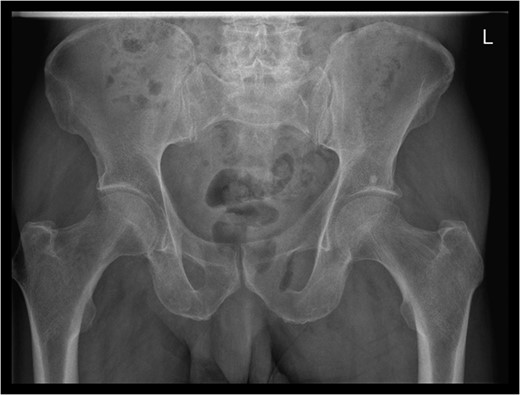

A rare complication of diverticular disease is the formation of fistulas, most commonly either colo-vesical or colo-vaginal. We present the unusual case of a perforated sigmoid diverticulum forming a colo-gluteal fistula and presenting initially as a gluteal abscess in an otherwise asymptomatic patient. After drainage of the gluteal abscess, the patient re-presented with faecal loss from the abscess drainage site. Imaging revealed fistulous communication between the sigmoid and the left obturator internus muscle, tracking to the gluteus maximus with associated abscess and cutaneous communication to the site of previous drainage. The patient underwent an emergency Hartmann's procedure with lay open/abscess drainage of the gluteal cavity. Post-operatively the patient experienced continuing discharge from the gluteal fistula despite repeated drainage and debridement causing considerable morbidity, inconvenience and misery. Clinicians should maintain a high index of suspicion when presented with a gluteal abscess and should consider the possibility of an intra-abdominal source.

A 67-year-old male was admitted to our acute unit with a 1-week history of a tender swelling over his left buttock/peri-anal margin. A course of oral antibiotics prescribed by his general practitioner had made no difference to his symptoms. He complained of severe pain in the left buttock associated with feverish symptoms. With hindsight, the pelvic/buttock pain seemed excessive compared with the outward appearance of the buttock swelling. He denied abdominal pain or alteration in bowel habit. His past medical history was significant for hypertension, atrial fibrillation, multiple previous myocardial infarctions and insertion of coronary stents. There was no past history of abdominal pathology.

Examination revealed a 2 cm area of tender erythema and induration over the left buttock/peri-anal region. There was also some bony tenderness noted on palpation of the left hip. Rectal examination was unremarkable.

The patient re-presented a week after discharge, complaining off persistent pain around the buttock, with feculent discharge and flatulence from the wound. Abscess cultures from the previous admission were reviewed and noted to have grown Escherichia coli and clostridium species.

An emergency Hartmann's procedure was performed under general anaesthetic through a lower midline incision as well as lay open of the perineal fistula. On opening the abdomen, a perforated diverticulum was identified extending into the left lateral pelvic wall. A standard Hartmann's procedure was performed, with sigmoid colectomy, division of rectum at recto-sigmoid junction and a tension-free stoma formed in left hypochondrium. The left buttock abscess cavity extended by a further 2–3 in. and the cavity then packed.